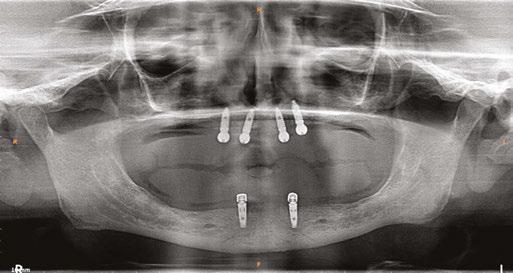

A 59-year-old male reported to the dental office with missing maxillary teeth due to poor oral hygiene. Treatment planning was done for all on four implant placements followed by prosthesis. A complete medical history was obtained and was negative for any significant medical problems. The patient denied being allergic to any medication as well. The patient agreed to the implant placement and was advised to have an orthopantomogram (Figure 1).

on the crest of the ridge in the region of teeth Nos. 15-25. While creating the incision, bleeding was noticed in the region of tooth No. 15 which intensified during the flap reflection (Figure 2). Bleeding was pulsatile, indicating an arterial bleed. Initially attempts to control bleeding included a pressure pack and ice pack, and the bleeder was isolated, and the vessel ligated (Figure 3). The bleeding could be controlled, and the procedure was completed by placing four Bioner implants (Bioner, Spain), size 4/10 mm. Sutures were placed, and patient was kept on basic medication for pain and infection control. Immediately after the surgery, the patient was advised to get a CBCT. As shown in Figure 4, a coronal view and Figure 4B (yellow arrows), the position of the artery can be seen.

In the follow-up sessions, the patient was comfortable, but did complain of mild swelling which subsided within 4-5 days. A post-op CBCT showed excellent recovery, bone width, and proper implant placement (Figure 5).

Figure 1: Pre-op panoramic radiograph Figure 2 (left): Alveolar antral artery (AAA). Figure 3 (center): The artery has been ligated with suture. Figures 4A and 4B (right): CBCT post-implant placement and position of the artery coronally (top). 4B. Showing the position of alveolar antral artery (AAA) in relation to implant placement as indicated by the yellow arrows (bottom)

Figure 5: Panoramic radiograph following implant placement